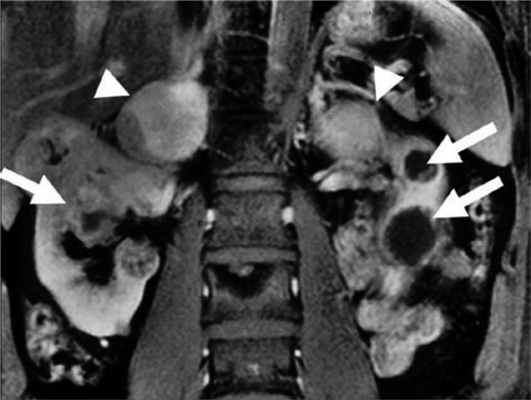

Феохромоцитома выявляется примерно у 26% пациентов с синдромом VHL [37]. У пациентов с очевидно спорадической феохромоцитомой в 3—11% случаев впоследствии выявляют мутацию VHL [10, 12, 13]. Феохромоцитома может быть первым проявлением синдрома [30, 72]. В большинстве случаев надпочечниковые феохромоцитомы при VHL-синдроме двусторонние (синхронные или метахронные) [37, 73]. Вненадпочечниковые феохромоцитомы встречаются примерно в 30% случаев [37, 74—76]. Феохромоцитомы как часть синдрома VHL имеют исключительно норадреналиновый фенотип. Биохимические маркеры опухоли могут помочь отличить VHL-ассоциированные феохромоцитомы от феохромоцитом при синдроме МЭН 2-го типа [75]. Различия в биохимическом фенотипе при VHL-синдроме и МЭН 2-го типа связаны с различной экспрессией тирозингидроксилазы (TH) — лимитирующего фермента синтеза катехоламинов, и фенилэтаноламин-N-метилтрансферазы (PNMT). У пациентов с синдромом VHL отмечена низкая экспрессия PNMT, преобразующей норадреналин в адреналин. Различия биохимического фенотипа также связаны с различиями хранения, транспорта и секреции катехоламинов [77]. МЭН 2-ассоциированные феохромоцитомы содержат более высокие концентрации катехоламинов из-за более выраженной экспрессии TH. VHL-ассоциированные феохромоцитомы, секретируют катехоламины непрерывно, тогда как при синдроме МЭН 2 отмечен эпизодический характер секреции. Это определяет и различия клинических проявлений двух синдромов. Например, пациенты с МЭН 2 чаще жалуются на кризовые подъемы АД [78]. Помимо генетических различий [26], регистрируется разная экспрессия эритропоэтина и его рецептора [79]. Кроме того, около 80% феохромоцитом бессимптомны и выявляются случайно при визуализирующих исследованиях. Низкая чувствительность некоторых радионуклидных методов визуализации может объясняться относительной нехваткой гранул хранения или уменьшенной экспрессией мембранного норадреналина или везикулярных моноаминных транспортеров [80]. Поэтому сцинтиграфия с 123 I-MIBG (метайодбензилгуанидином) часто не обнаруживает VHL-связанные надпочечниковые феохромоцитомы [81, 82]. ПЭТ с 6-18F-фтордопамином более чувствительный метод [36, 83]. Злокачественные феохромоцитомы с метастазами в легких, печени, костях, лимфоузлах редко встречаются при синдроме VHL [37, 74, 84—87]. Метастазы выявляются менее чем в 7% случаев [37]. К сожалению, в настоящее время нет четких признаков, позволяющих надежно отличить доброкачественную от злокачественной феохромоцитомы, хотя уже известно, что герминальная мутация гена SDHB, является в этом отношении точным маркером [86—88]. Выявление феохромоцитомы у пациентов с синдромом VHL особенно важно, учитывая высокую вероятность хирургических вмешательств по поводу других опухолей (гемангиобластом ЦНС и др.). Невыявленная феохромоцитома при других вмешательствах может привести к опасным для жизни гипертоническим кризам. Более 70% феохромоцитом у детей являются VHL-ассоциированными. Каждому пациенту с VHL-синдромом и подтвержденной феохромоцитомой до оперативного лечения необходимо проводить ПЭТ с 6-18F-фтордопамином или сцинтиграфию с 123 I-MIBG для выявления вненадпочечниковой феохромоцитомы или метастазов [89]. Лечение феохромоцитомы оперативное. В то же время 6-месячная терапия ингибиторами тирозинкиназы приводит к уменьшению опухоли на 21% и сокращению уровня норметанефринов и хромогранина А в плазме [90] (рис. 4). Рисунок 4. Двусторонняя феохромоцитома и поликистоз почек.